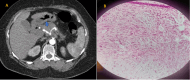

Figure 4

Figure 4. (A) Axial contrast-enhanced CT scan image in arterial phase demonstrates small hyperenhancing lesion in the tail of the pancreas. (B) Solid nests, trabeculae, and cords of tumor cells having eosinophilic to amphophilic, finely granular cytoplasm and monomorphic centrally located round to oval nuclei with salt and pepper appearance (H&E stain, original magnification 40×). It was determined to be a case of insulinoma

CT: computed tomography; H&E: hematoxylin and eosin